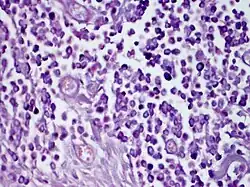

| Solitary mastocytoma. | |